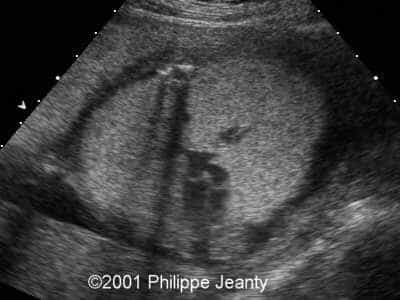

This 2nd trimester fetus has the following images (actually, these images remained unchanged for several weeks)

• very enlarged lungs on both sides

• inversion of the diaphragm that is convex towards the abdomen

• small compressed heart

• ascites but no generalized hydrops (no skin thickening for instance)

A much more common diagnosis for a bilateral echogenic lung associated with microcardia and ascites (Budd-Chiari phenomenon) is Larynx, atresia or as reported by several the CHAOS syndrome which stands for Congenital High Airway Obstruction Syndrome (which is typically laryngeal or tracheal atresia). This is the diagnosis that was indeed suspected in this fetus.

The patient was then referred to Dr. Ruben Quintero who managed to pass an endoscope in the fetal trachea. He created an opening, but unfortunately was not able to create a communication between the proximal and distal portion of the larynx, instead ending in the thoracic cavity. The fetus did well after the surgery (no premature delivery), although there was no improvement, and after a few more weeks of worsening of the lung condition the parents elected to terminate the pregnancy.